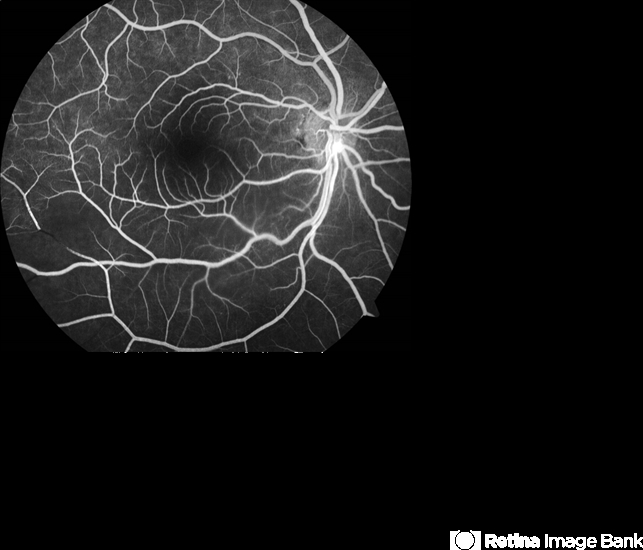

- CRAO BRAO

- branch retinal artery occlusion (BRAO), arterial embolus

- FFA of the patient confirming inferotemporal BRAO and also demonstrating the embolus in the retinal artery at the disc.